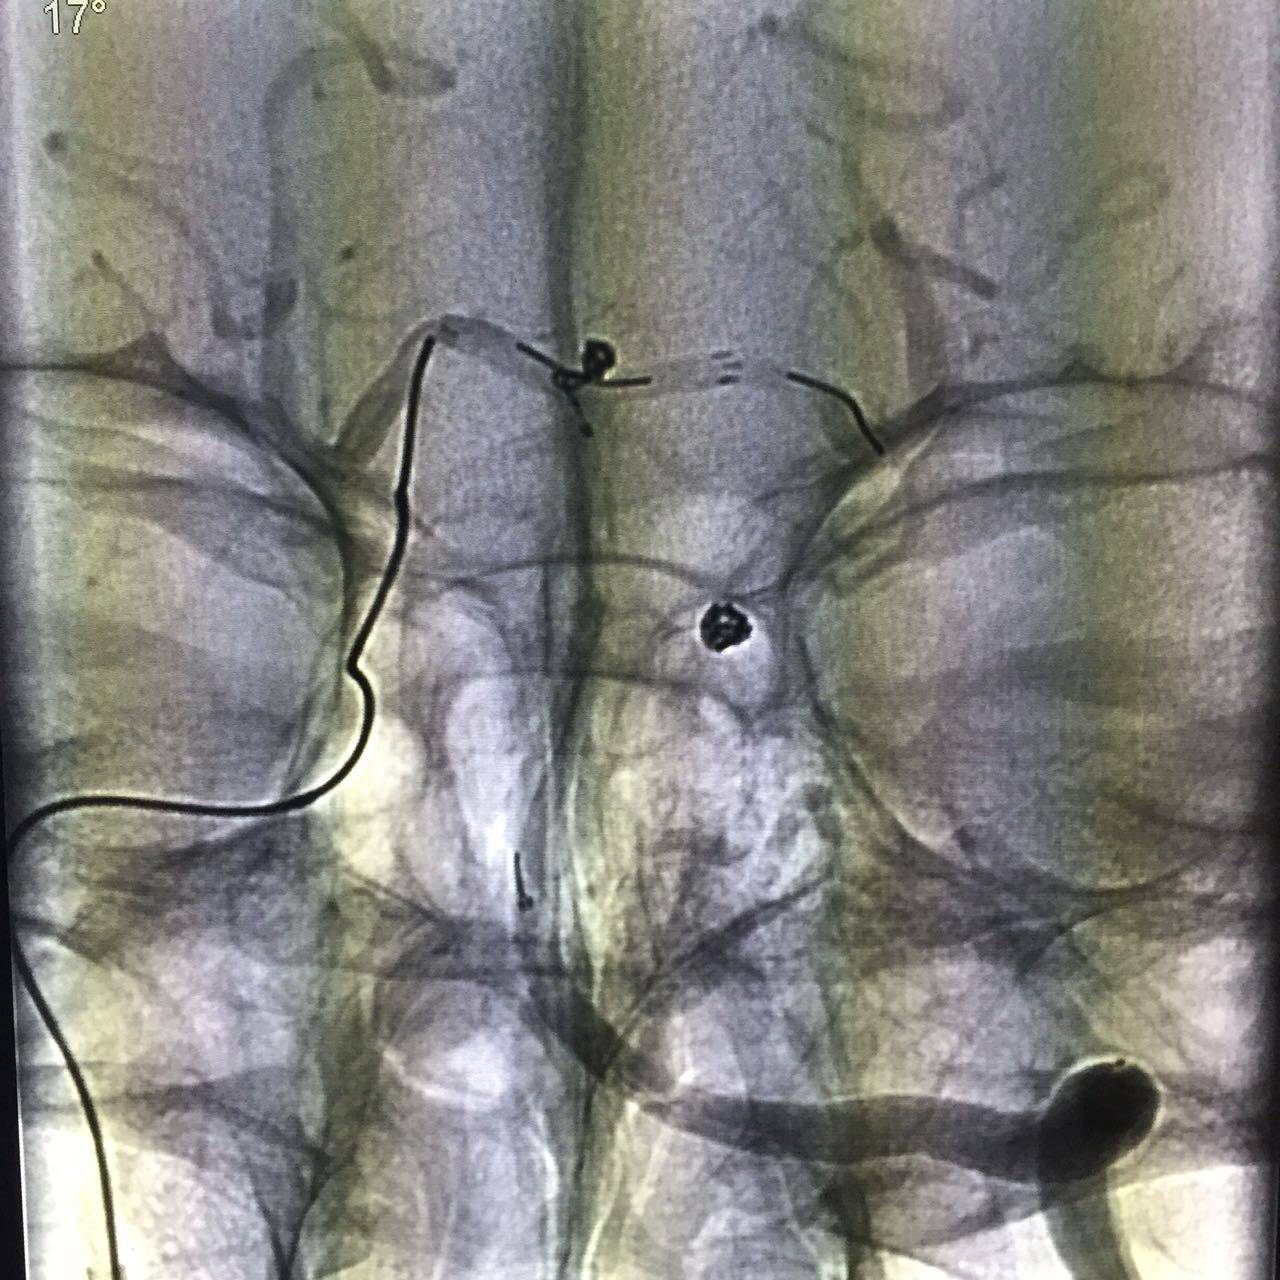

再次行左侧股动脉穿刺,引入另一根指引导管进入右侧颈内动脉,将一根Prowler Select Plus支架导管通过右侧颈内动脉、后交通动脉、右侧大脑后动脉到达左侧大脑后动脉P2段。再将SL-10微导管通过置入左侧椎动脉的另一根指引导管到达动脉瘤腔,选择Enterprise 4.5mmx14cm支架跨瘤颈放置,采用半释放技术,选择一枚Delta paq 1.5mmx4cm栓塞动脉瘤两个瘤囊。

动脉瘤填塞完毕后,完全释放支架保护瘤颈。

术后造影动脉瘤均未显影,载瘤动脉通畅。